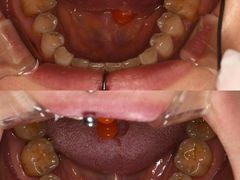

• 固瑞齿科(国贸门诊店)

• -固瑞齿科(国贸门诊店)

匿名用户 | 24-06-12